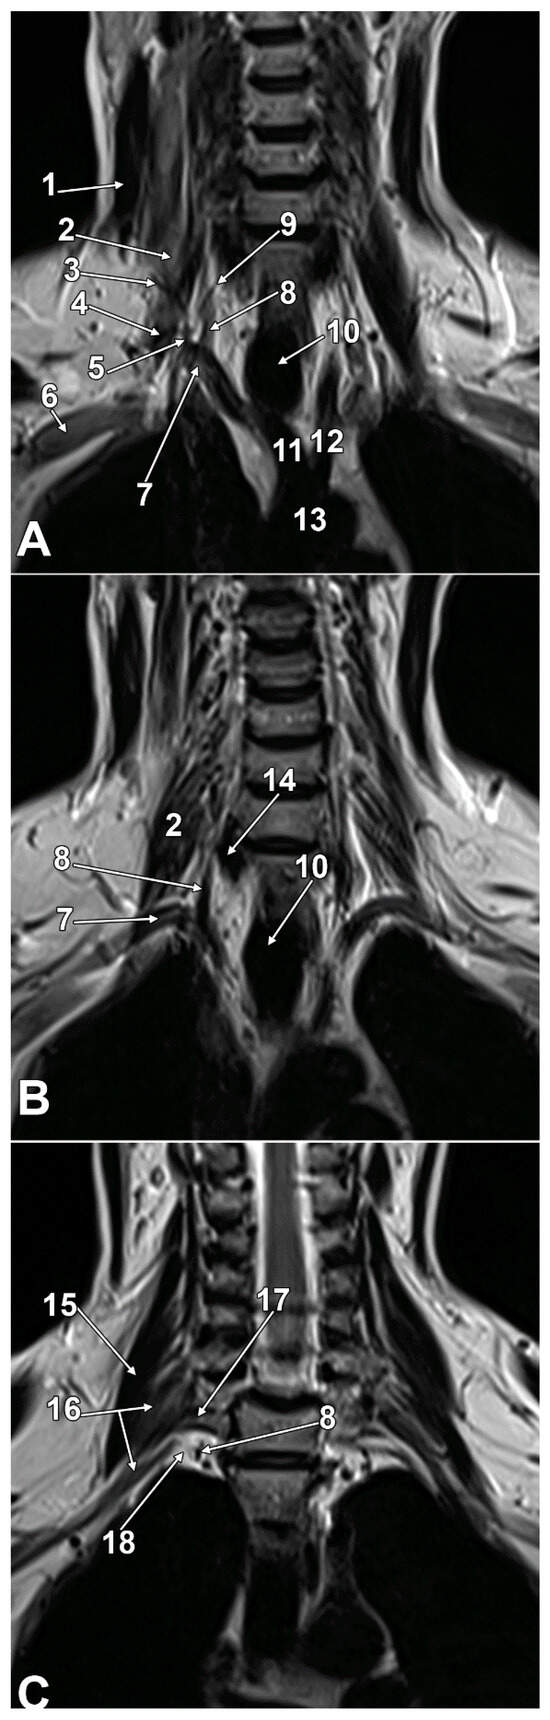

Anatomy, Imaging, and Clinical Significance of the Cervicothoracic (Stellate) Ganglion

Background/Objectives: The stellate ganglion (SG), formed by the fusion of the inferior cervical and first thoracic sympathetic ganglia in approximately 80% of individuals, plays crucial roles in cardiac innervation, pain management, and autonomic regulation. This review examines the anatomical variations, histological structure, clinical applications, and therapeutic implications of the SG and stellate ganglion block (SGB), presenting original high-resolution magnetic resonance imaging (MRI) evidence of SG visualization, an underutilized approach in autonomic nervous system research. Methods: We conducted a comprehensive literature review of anatomical, physiological, and clinical studies on the SG, incorporating original anatomical dissections and high-resolution MRI. Contemporary research on SGB applications, complications, and mechanisms of action was analysed and correlated with imaging characteristics. Results: The SG demonstrates significant anatomical variability, including the presence of intermediate ganglia, accessory nerve pathways, and variable relationships with surrounding vascular structures. Our original MRI imaging consistently identified the SG at the thoracic inlet, anterior to the neck of the first rib, lateral to the longus colli muscle, and posterior to the vertebral artery, demonstrating that advanced imaging can reliably visualize this critical autonomic structure and its anatomical variants. Histologically, it contains typical sympathetic architecture, comprising postganglionic neurons, satellite glial cells, and specialized SIF cells that modulate ganglionic transmission. SGB shows therapeutic efficacy across diverse conditions, including cardiac arrhythmias, chronic pain syndromes, post-traumatic stress disorder, sleep disorders, and immune dysfunction. The procedure’s mechanisms involve both direct sympathetic blockade and complex neuroimmune pathways that affect central autonomic centers and lymphoid organs. Complications include vascular injury, pneumothorax, and nerve blocks affecting the recurrent laryngeal and phrenic nerves. Conclusions: The SG represents a critical autonomic structure with expanding clinical applications. This work advances the field by demonstrating that high-resolution MRI can consistently and non-invasively visualize the SG and its anatomical variations, knowledge previously mostly limited to cadaveric studies. Understanding these imaging-defined anatomical variations is essential for optimizing therapeutic interventions. Advanced imaging guidance integrated with comprehensive anatomical knowledge is crucial for maximizing efficacy while minimizing complications in stellate ganglion block procedures. Full article

Figure 1